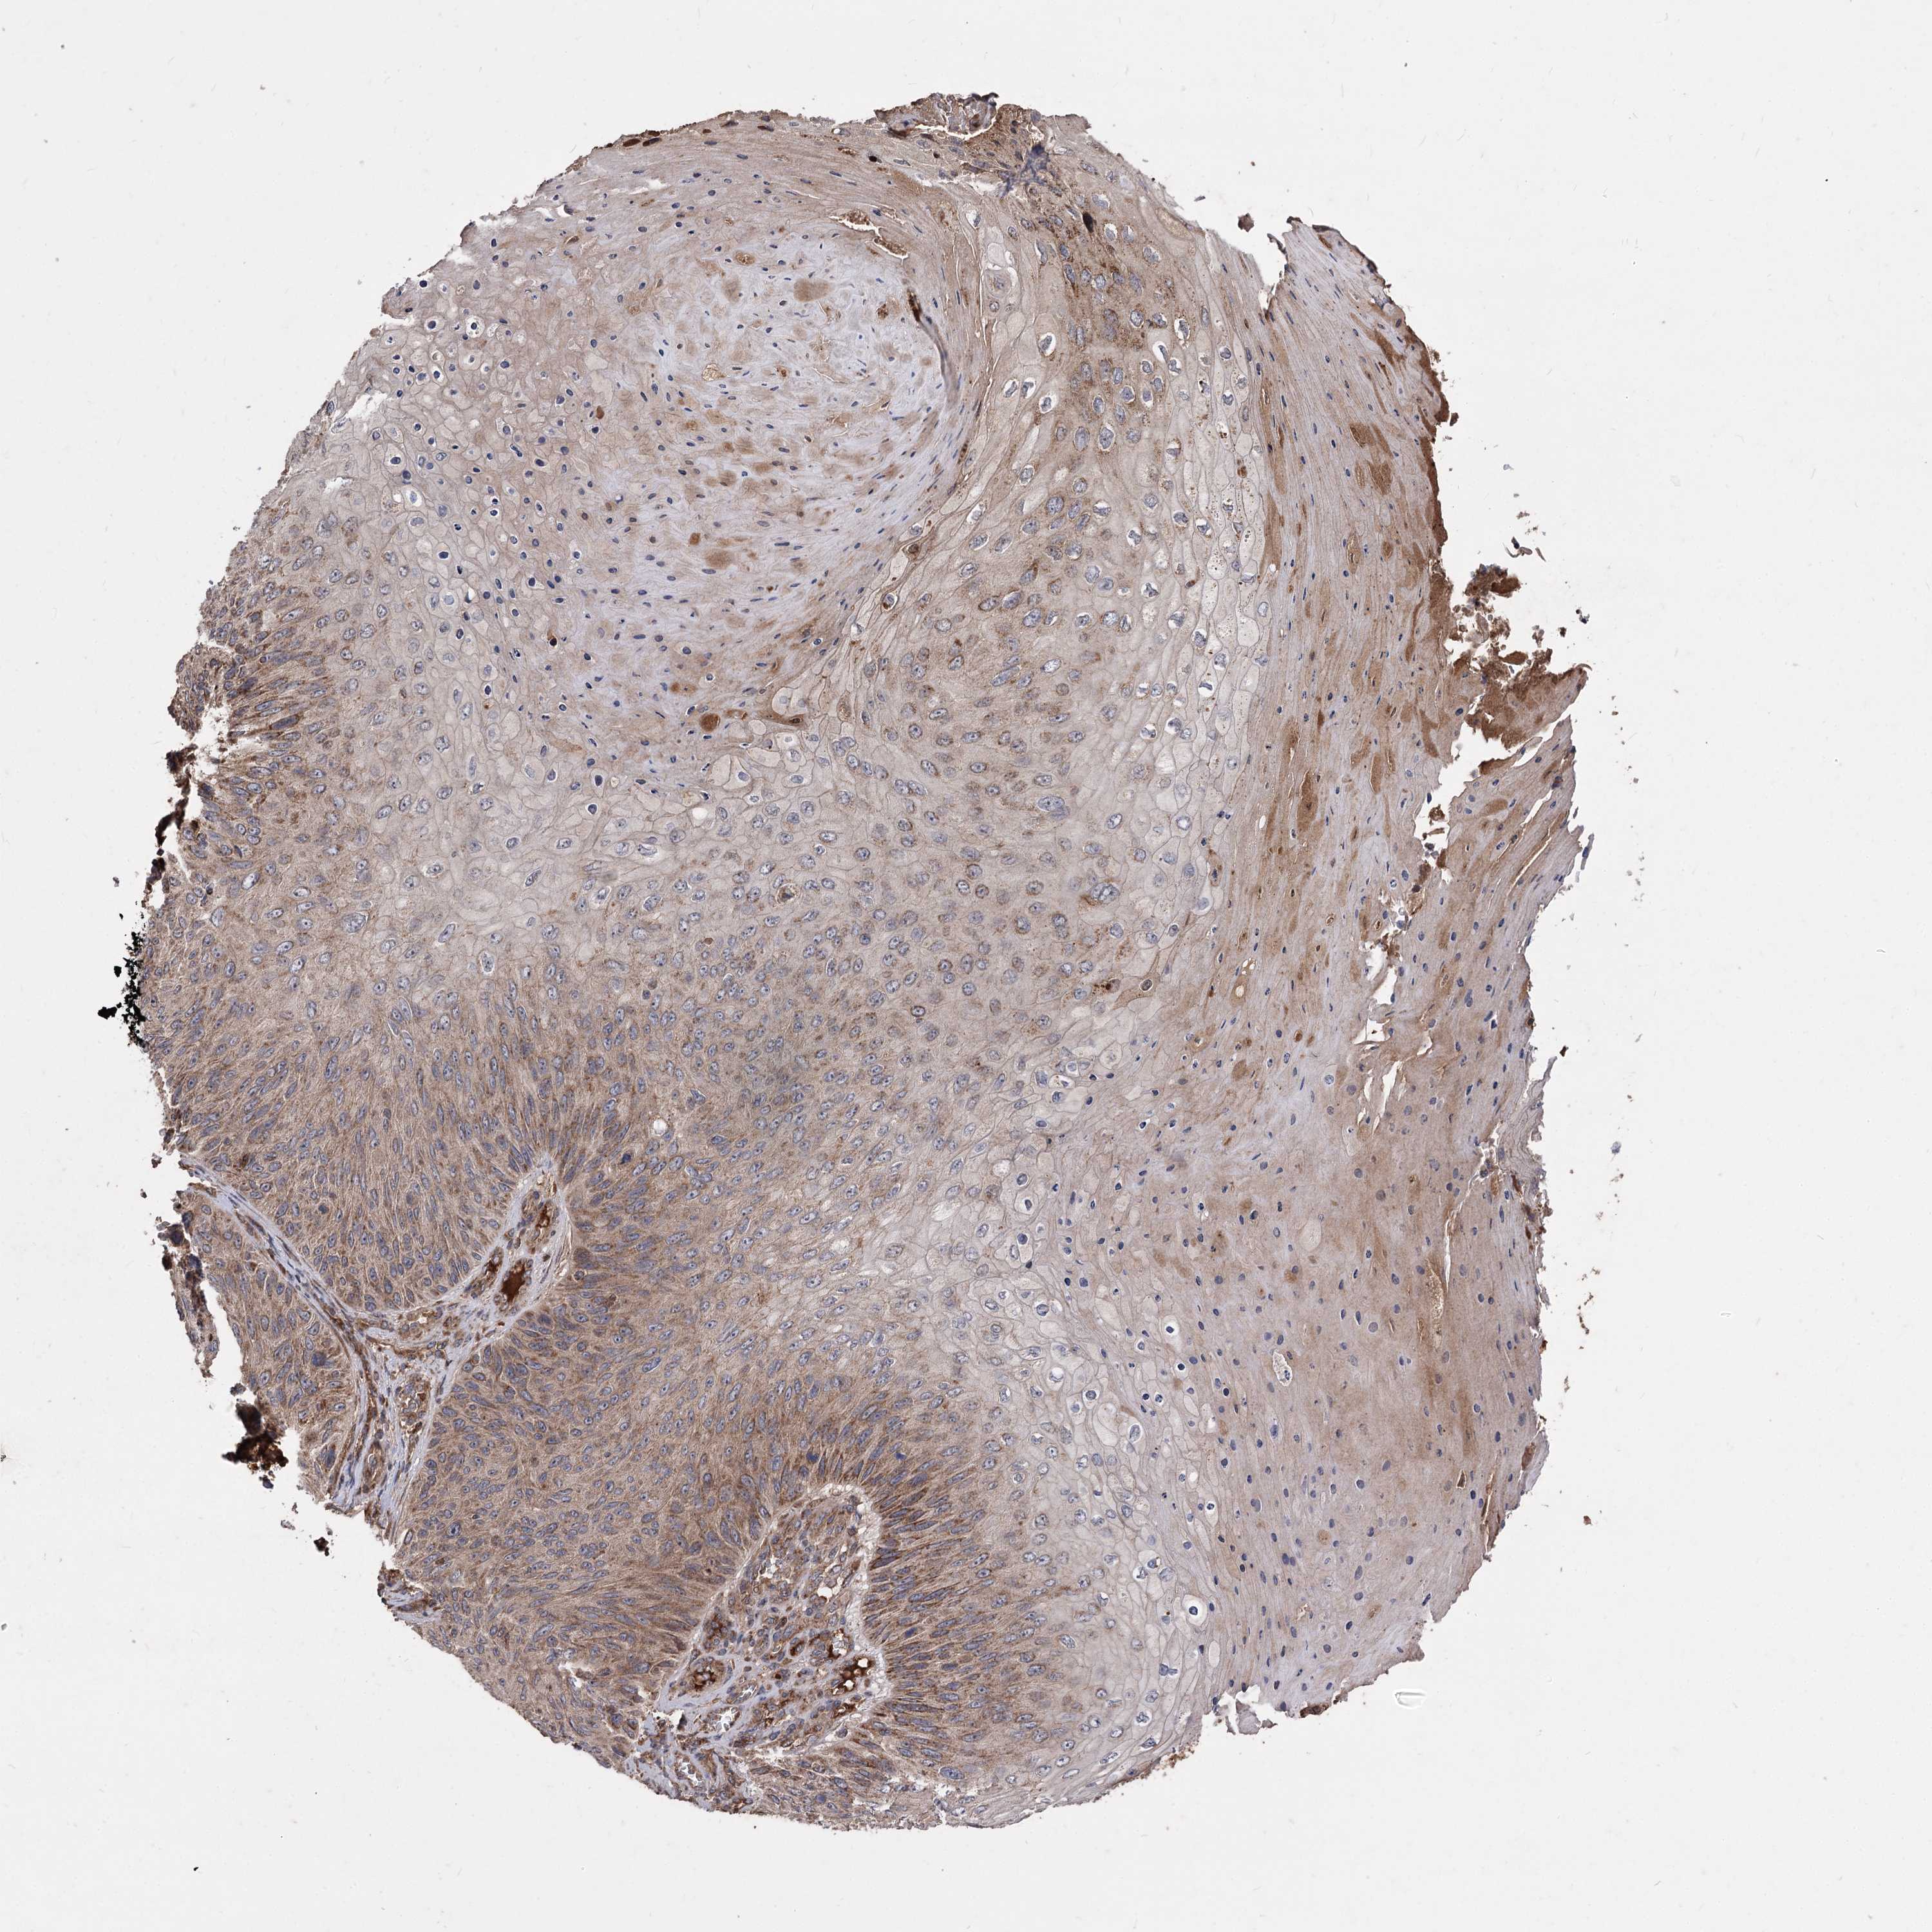

SKIN CANCER - Protein expressioni

A mouse-over function shows sample information and annotation data. Click on an image to view it in a full screen mode. Samples can be filtered based on level of antibody staining by selecting one or several of the following categories: high, medium, low and not detected. The assay and annotation is described here.

Antibody staining in the annotated cell types in the current human tissue is reported as not detected, low, medium, or high, based on conventional immunohistochemistry profiling in selected tissues. This score is based on the combination of the staining intensity and fraction of stained cells.

Each image is clickable and will lead to virtual microscopy that enables deeper exploration of all samples and also displays staining intensity scores, fraction scores and subcellular localization as well as patient and tissue information for each sample.

Squamous cell carcinoma, NOS